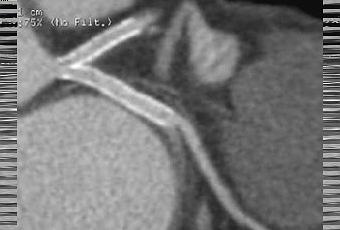

Contrôle systématique d'une angioplatie à 6 mois du tronc commun: resténose non significative (hypodensité intrastent) du stent commun IVA et du stent de la circonflexe proximale. In Annales de Cardiologie et d'Angéiologie Volume 56, Issue 7,December 2008, Pages 359-354